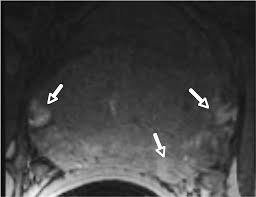

Imaging On Nodal Staging Of Prostate Cancer Future Oncology

Imaging On Nodal Staging Of Prostate Cancer Future Oncology from www.futuremedicine.com